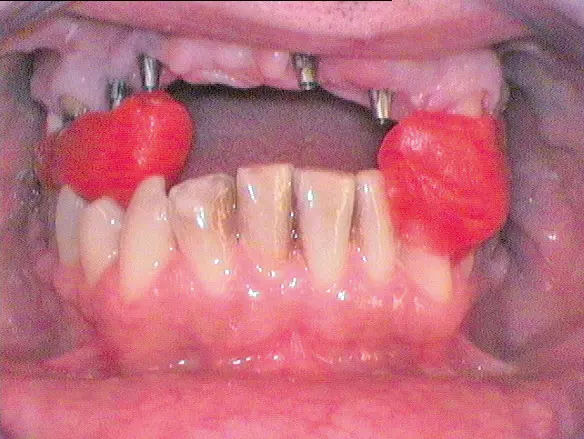

Nach dem Entfernen der insuffizienten Versorgung von 14 auf 22, stellten sich die Zähne 14, 13, 21 und 22 als nicht erhaltungswürdig heraus. Präoperativ wurde ein Eierschalenprovisorium gefertigt, welches im März 2015 auf den Zähnen 15 und 23 sowie auf temporären Implantaten regio 013, 014, 021 und 022 (Bone Trust® mini, Medical Instinct, Bovenden) intraoperativ angepasst und verankert werden sollte (vgl. Abb. 8-13). Im Verlauf des Eingriffs, bei dem die genannten Zähne operativ entfernt wurden, zeigten sich ausgedehnte radikuläre Zysten, die mit einer Resorption der vestibulären Knochenlamelle einhergingen und ektomiert werden mussten (Abb. 4-6).

Geplant war, dass die temporären Implantate während der Einheilzeit des Knochenblocks belassen werden können, um die augmentierten Regionen vor mechanischer Belastung zu schützen. Entgegen dieser ursprünglichen Planung mussten sie jedoch aufgrund der ausgedehnten vertikalen Augmentation von crestal ca. 3 mm entfernt werden. Eine druckfreie Einheilung des Augmentats war dennoch gewährleistet, da das Langzeitprovisorium metallverstärkt war und auch auf den natürlichen Zähnen 16 und 23-25 durch die Geschiebekonstruktion und durch das Ausschleifen an der Basis spannungsfrei fixiert werden konnte (Abb. 8-13). Eine perioperative antiinfektiöse Therapie erfolgte mit einer intravenösen Gabe von 600 mg Clindamycin, gefolgt von Clindamycin 600 mg 1-1-1 oral über 10 Tage postoperativ. Sechs Wochen postoperativ ließ sich bereits klinisch die Ausrundung des OK-Bogens durch das Knochenblocktransplantat erkennen (Abb. 23).